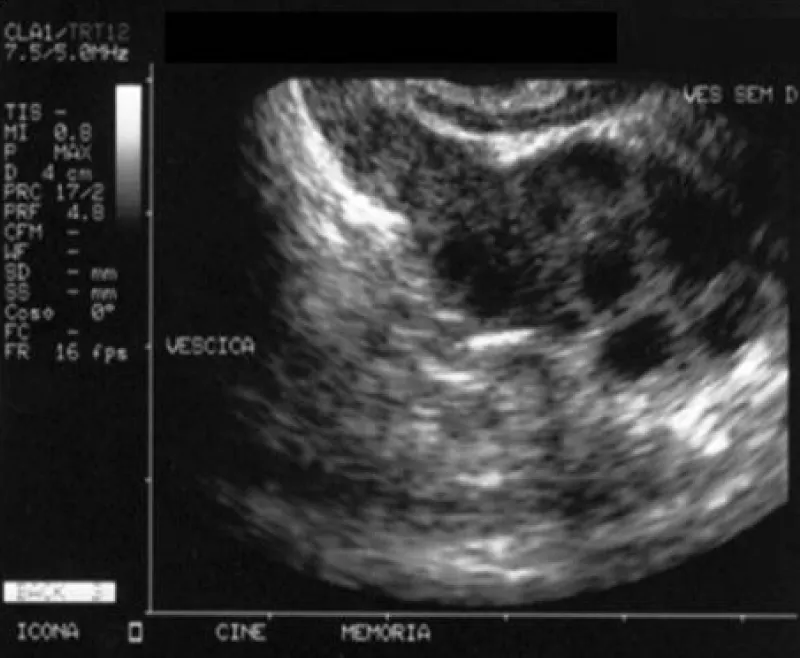

Figure 8: From J Urol Res 12(1): 1161.

A case of an adult, 120 kg, age 60 years old, diabetes type II controlled with therapy, history of recurrent chronic prostatitis (more than 20 years, every 3 months, but also more frequent).

Normal flux if not congested, light ureteral restriction confirmed by retrograd uretroghraphy, abnormal urinary fluxumetry. Ecographic prostate: microcalcification present, and seminal vesicle volume increased.

Through the transrectal ultrasound of the prostate, it is possible to see oedema, dilatation of the seminal vesicles and ejaculatory ducts, and intraprostatic calcifications.

Imaging (transrectal ultrasound) can show seminal vesicle enlargement.